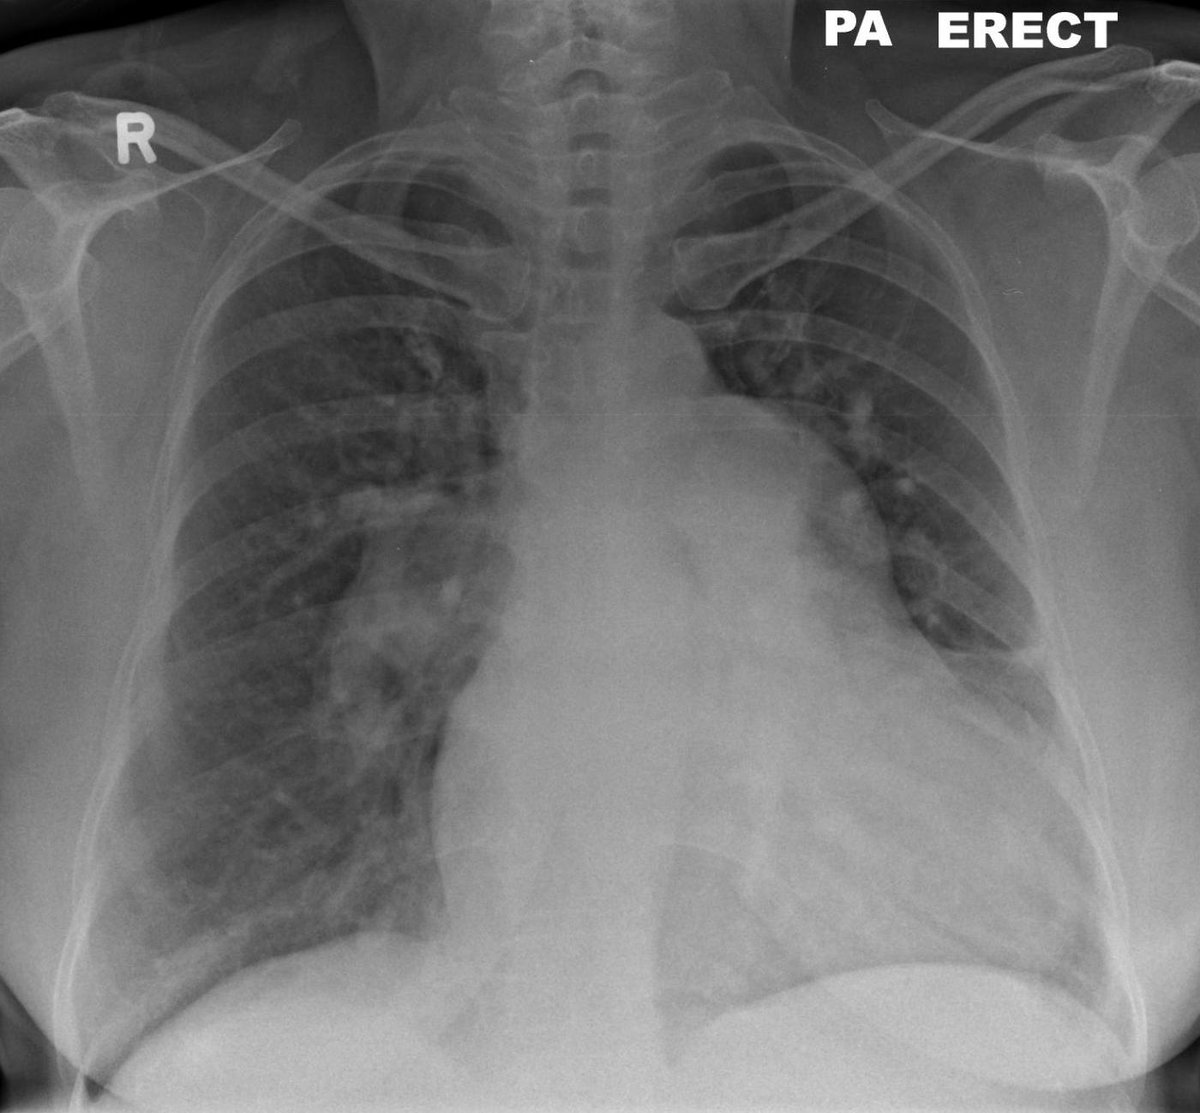

🔴 Mónica Ibarra, hija de Martha Zamorano “Miss Leti”, denuncia que tras años de negligencia y un diagnóstico tardío de fibrosis pulmonar, en el IMSS y en el INER solo les ofrecieron tratamiento paliativo. “Cuando llegamos con el neumólogo del siglo XXI nos dice que no existe el protocolo, que no hay trasplante pulmonar aquí en la Ciudad de México y mucho menos por parte del INER”, pese a que su mamá sí es candidata. El único procedimiento viable está en Monterrey, en el hospital privado Christus Muguerza con un costo superior a los 5 millones de pesos, además de estudios iniciales de hasta 300 mil y la necesidad de mudarse. A esto se suma que su mamá fue registrada con salario mínimo ante el IMSS, por lo que hoy recibe una incapacidad muy baja. ⚠️ Se hace un llamado a @nadgasman y @SSaludCdMx para atender el caso de Miss Leti y brindar apoyo a su familia ante esta situación. 👉La familia inició una campaña para recaudar fondos y poder realizar el trasplante. Aquí puedes apoyar: gofund.me/eb4ce2a21 También piden apoyo en sus redes @pulmonesparamisslety #AzucenaxFórmula